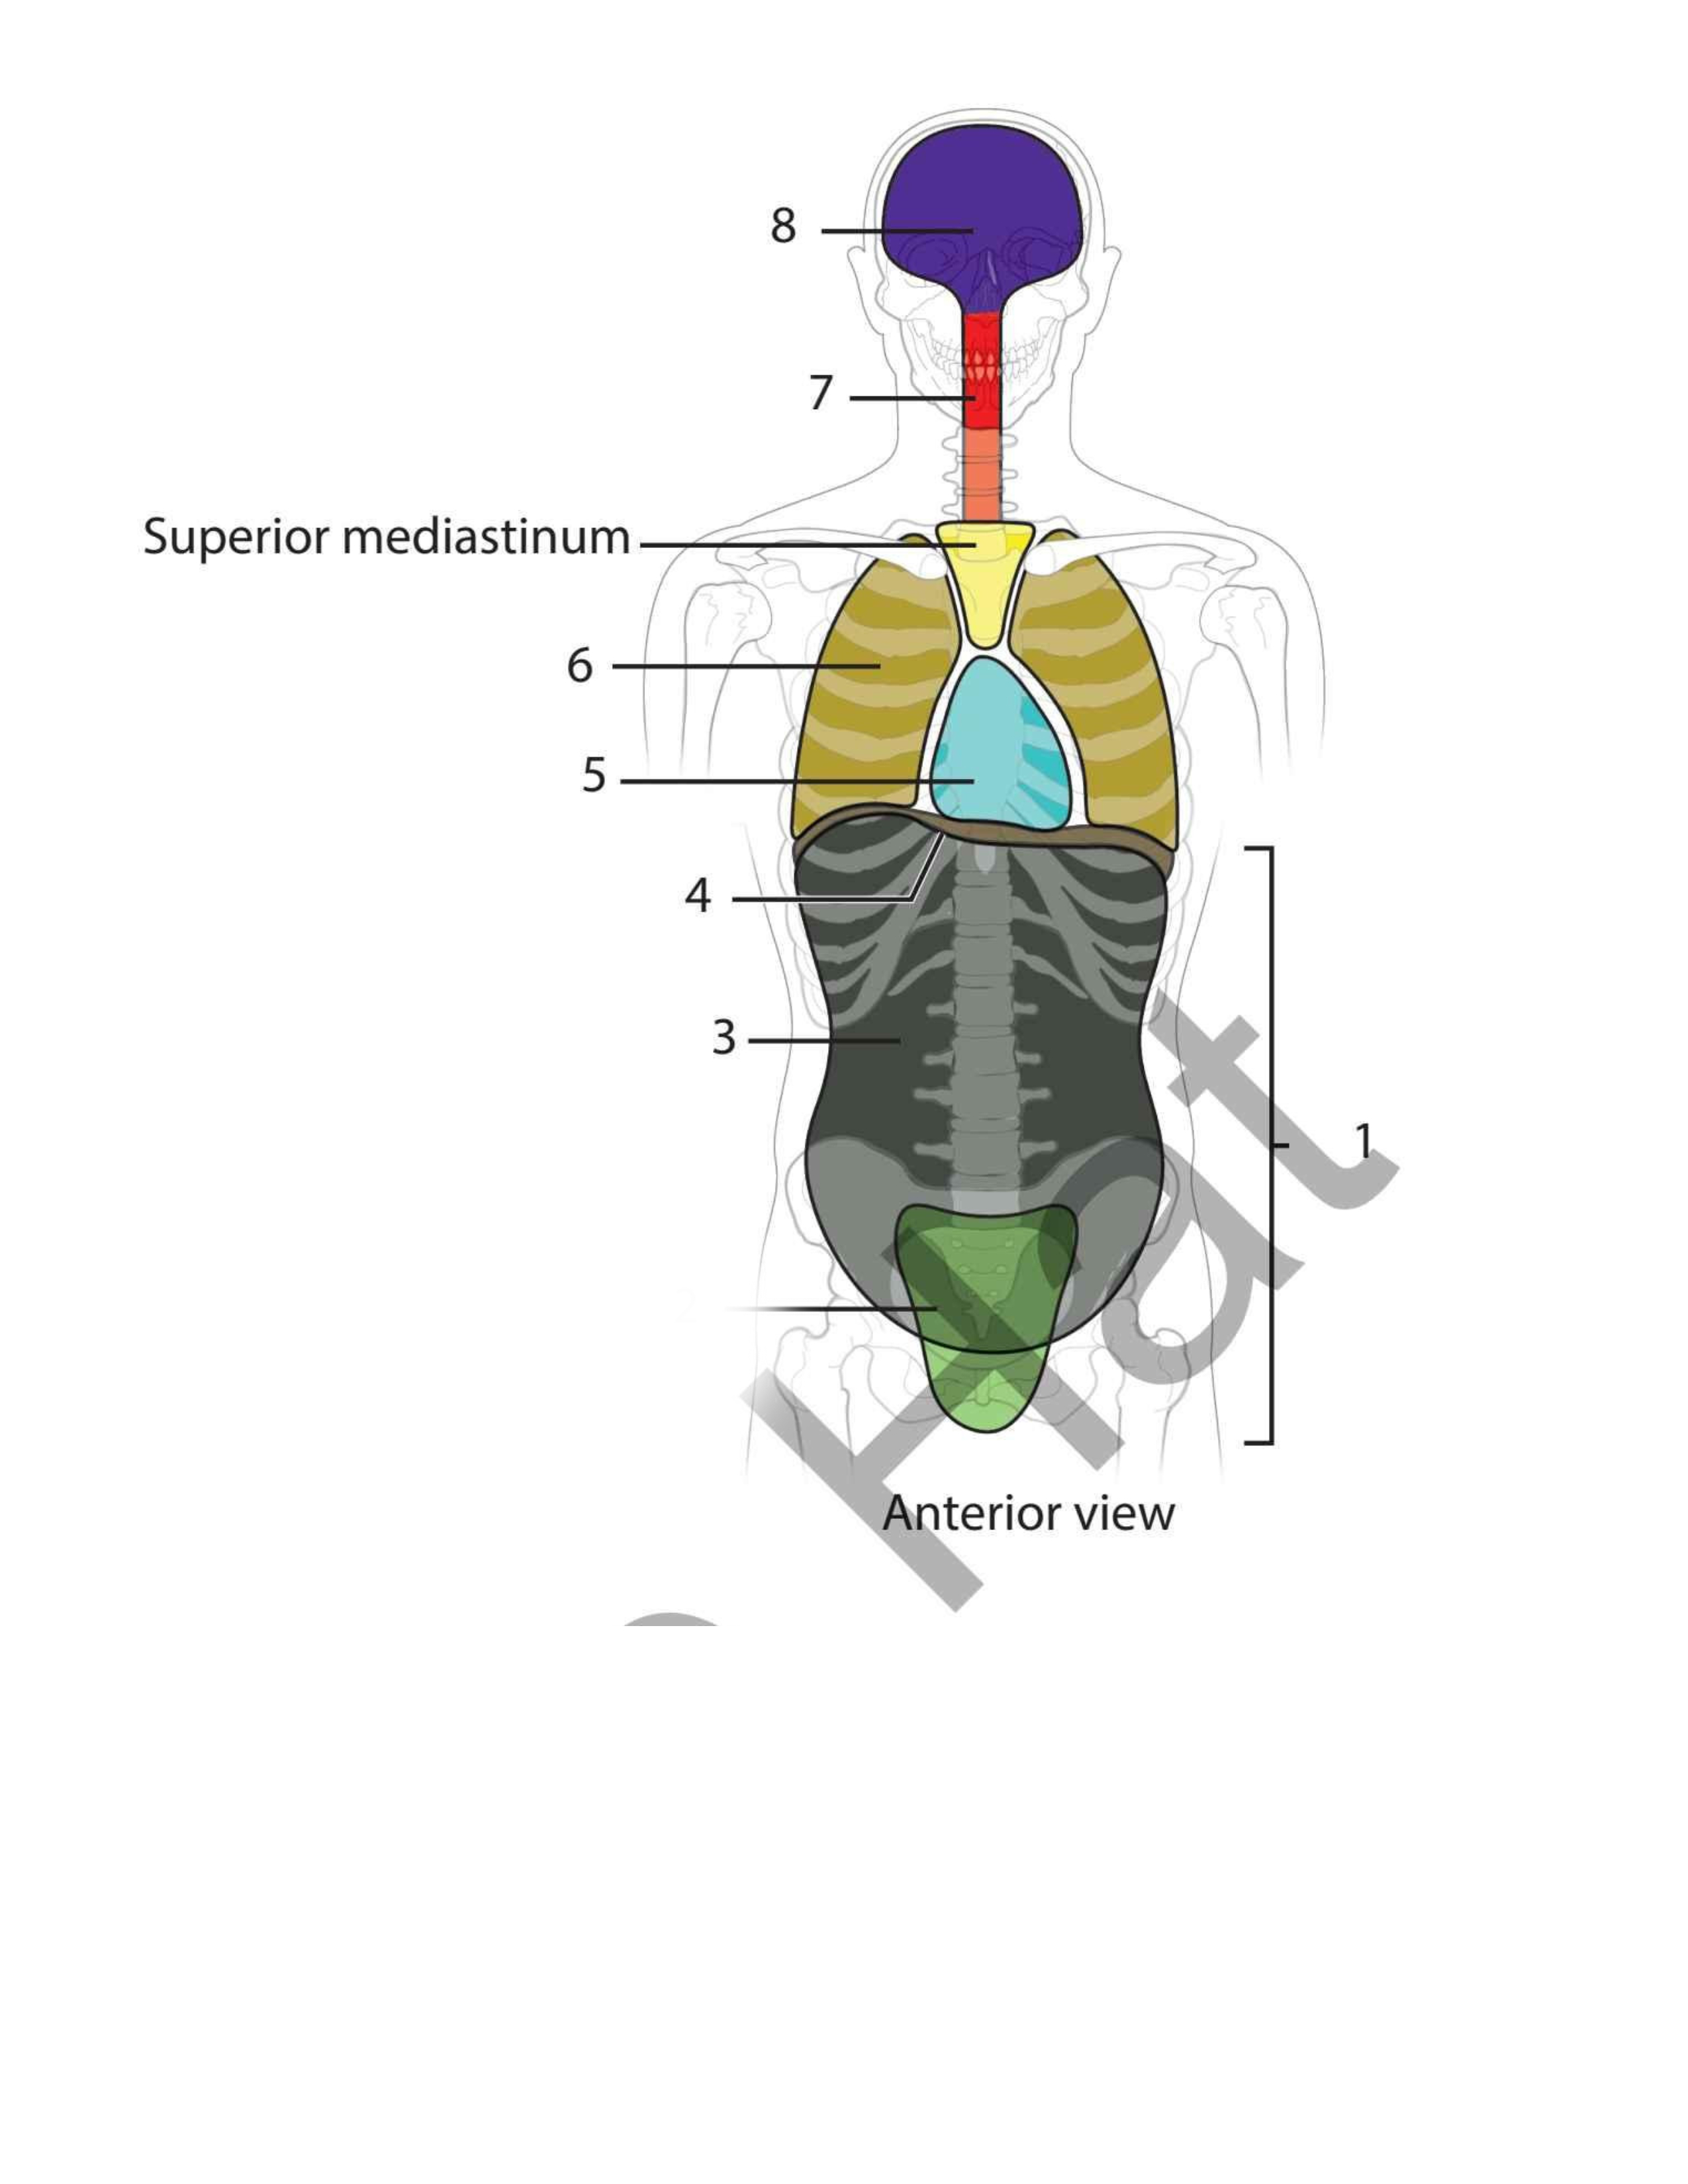

Pelvic

Abdominal

Diaphragm

Pericardial

Pleural

Vertebral

Cranial